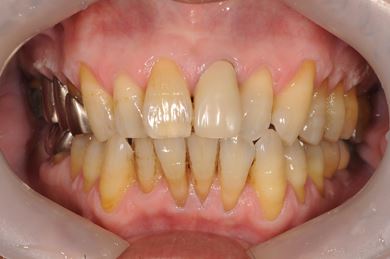

| 性別/年齢 | 男性 / 60歳 | ||||||||||||||||||||||||||||||||

| 主訴 | 右下奥歯の治療相談。(痛み・ぐらつき・物がかめない) | ||||||||||||||||||||||||||||||||

| 治療方針 | 左下奥の欠損部分をインプラント治療にて、機能的・審美的に回復を行う。 | ||||||||||||||||||||||||||||||||

| 治療内容 | インプラント2本、メタルボンドセラミッククラウン2本 | ||||||||||||||||||||||||||||||||

| 総治療費 | 680,610円 | ||||||||||||||||||||||||||||||||

| 治療期間 | 7ヶ月 |